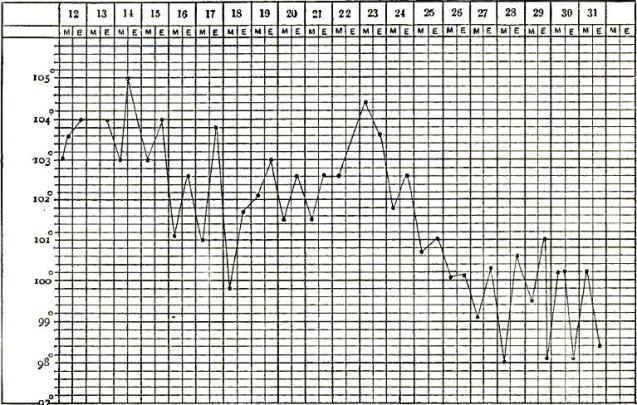

| 20. | TEMPERATURE CHART OF TYPICAL CASE OF RELAPSING FEVER, WITH THREE RELAPSES TERMINATING IN RECOVERY |

| 21. | TEMPERATURE CHART OF TYPICAL CASE OF RELAPSING FEVER, TERMINATING IN RECOVERY |

| 22. | TEMPERATURE CHART FROM A CASE OF THE BILIOUS TYPHOID OR GRAVE SUBINTRANT FORM OF RELAPSING FEVER |

| 23. | TEMPERATURE CHART SHOWING THE LAPSE OF A REMITTENT FEVER INTO AN INTERMITTENT |